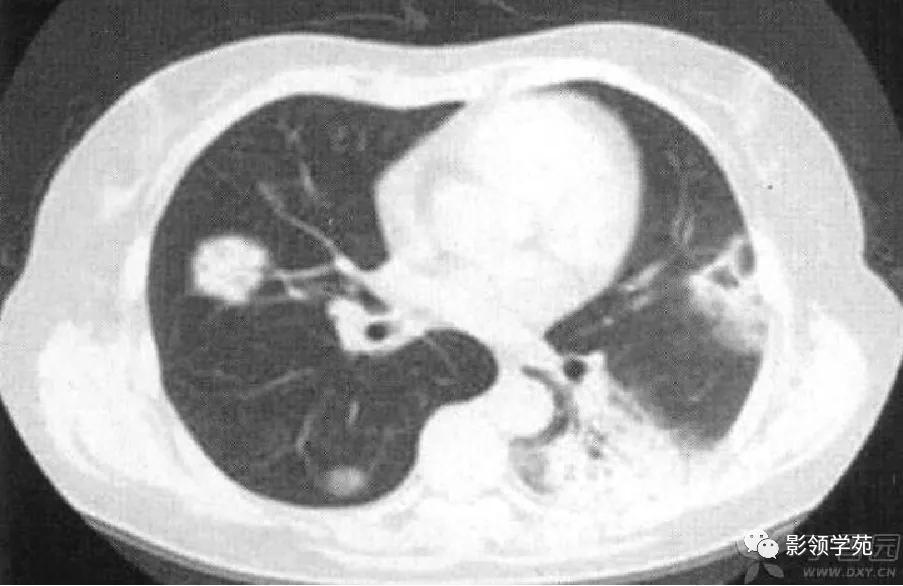

病例3:双肺多发结节伴空洞,部分空洞见气液平面。

病例4:左肺斑片状实变,右肺中下叶结节灶,中叶结节见供养血管征。